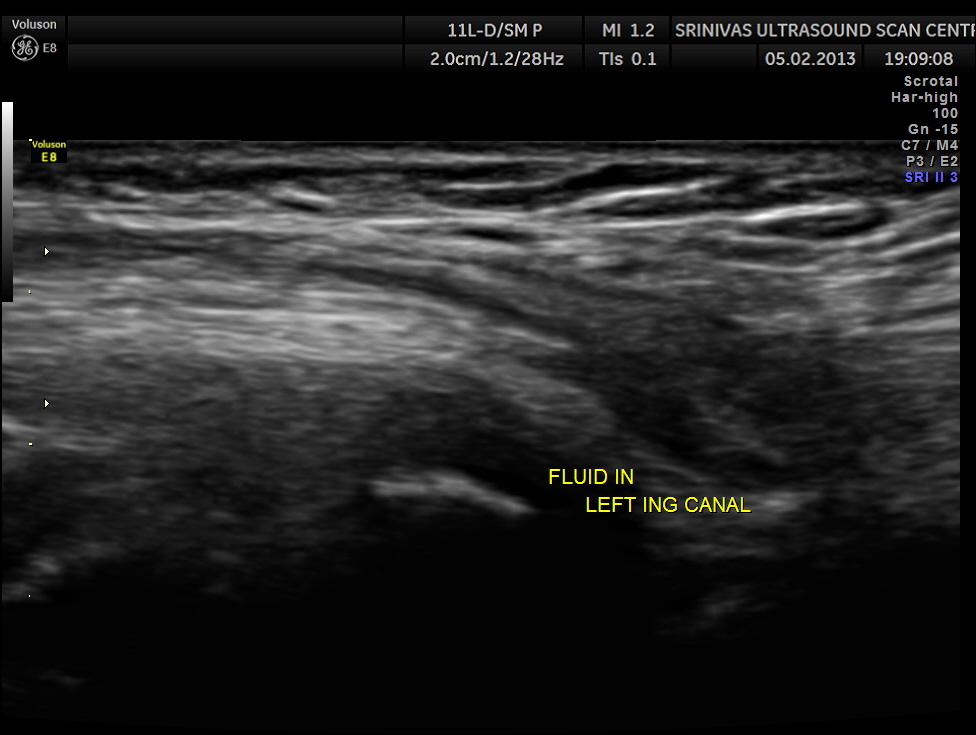

This was a 11 year old boy referred for evaluation of left inguinal swelling on and off.

The clinical diagnosis was bubunocele.

(medicine) An inguinal hernia, especially of the incomplete variety in which the hernial pouch descends only as far as the groin, forming a swelling there like a bubo.

An inguinal hernia, especially one in which the knuckle of intestine has not yet emerged from the external abdominal ring.